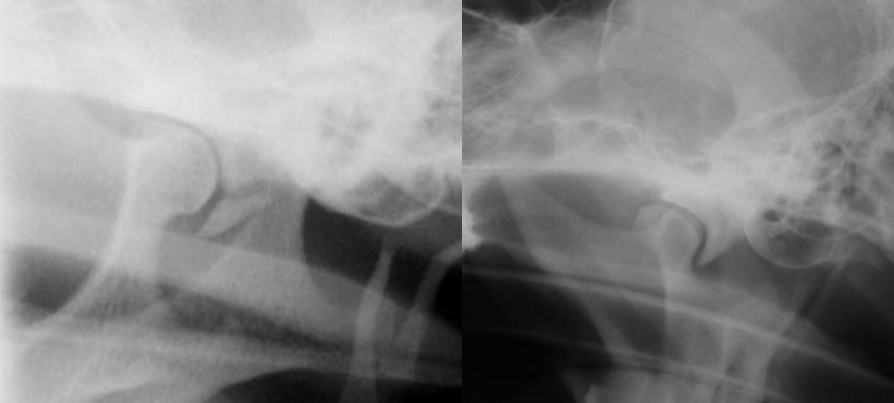

19

Q

identify pathology

A

calvarium neoplasia in left image

mandibular neoplasia in right side image

20

left image: Fracture of retroauricular processus

right: TMJ dysplasia

21

TMJ neoplasia

but note that osteomyelitis can look very similar

22

TMJ subluxation

in the closed mouth image the luxation is difficult to discern but in the open mouth view its obvious